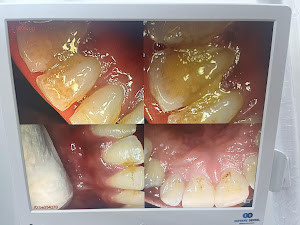

Welcome to our gallery

See how our company transforms ideas into reality. This gallery is a visual testament to our work and achievements.